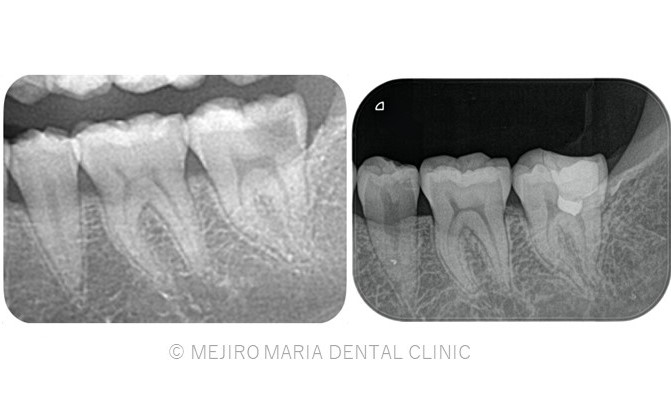

【症例】生活歯髄保存療法を用いて歯髄保存した症例−歯の神経を保存できる虫歯処置−